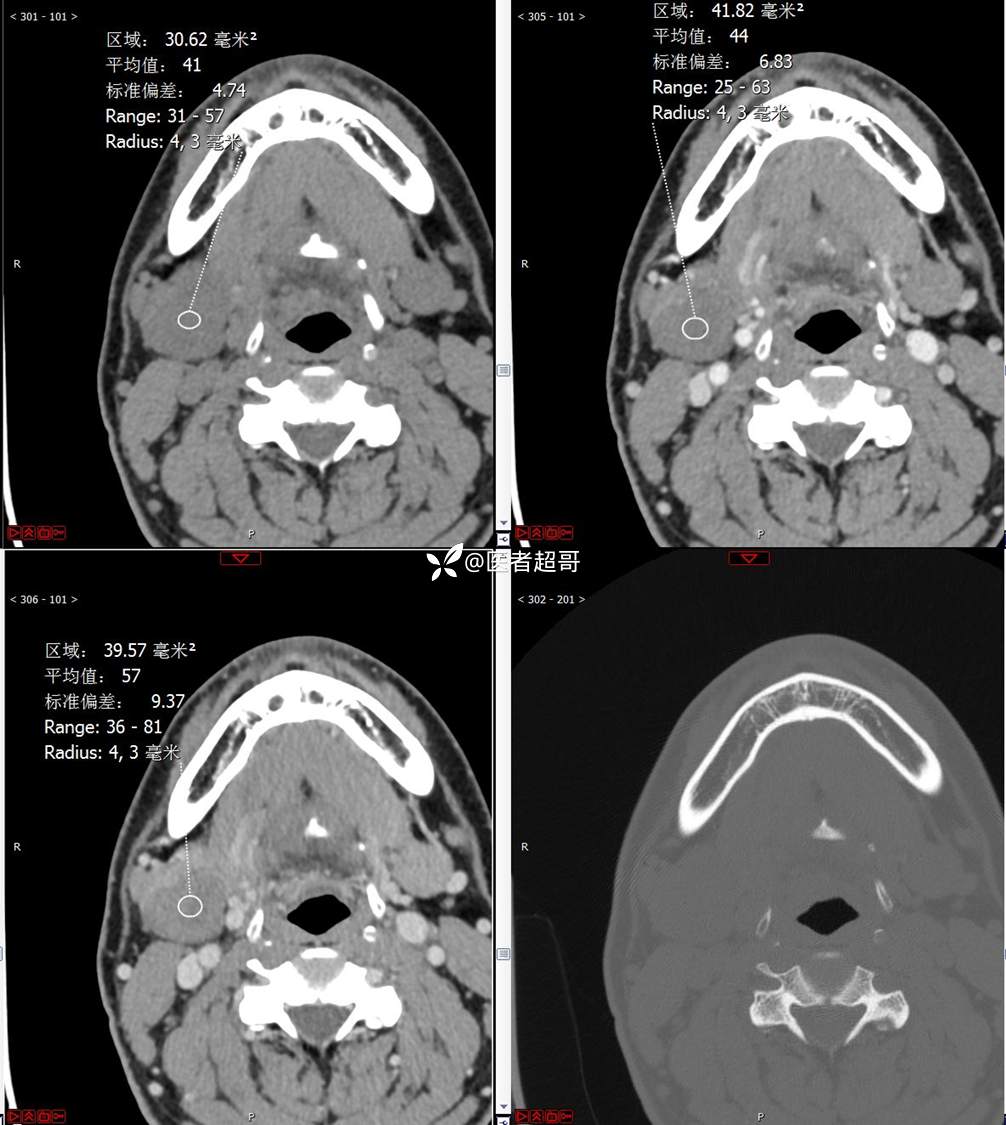

颌下腺结节:青年男性,颌下区无痛性肿物,请分析~~~

主 诉:发现右颌下区无痛性肿物1年。

现病史:患者于1年前发现右颌下区一肿物,肿物约“葡萄粒”大小,无疼痛不适,无进食时颌下区肿胀及疼痛不适。2023-10-1就诊于市中医院行超声检查;未予治疗。肿物体积无明显变化,求进一步治疗就诊于我院门诊,门诊以“颌下肿物”收入我科。患者自发病以来,神志清,精神佳,食欲好,睡眠好,大小便正常,近期体重无明显变化。